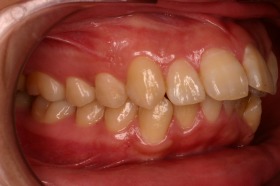

歯の矯正治療 症例ビフォー&アフター

ご覧の症例は出っ歯を矯正治療でキレイにしたケースです。

このような場合では歯を抜いて矯正するか

、抜かずに矯正するか分かれるケースです。

ご覧の矯正歯科治療の場合は、抜いて矯正歯科

治療していますが東京世田谷矯正歯科センターでは

非抜歯矯正歯科治療をベースにしています。

どうしても抜かないとキレイにならない場合のみ

抜歯して矯正歯科治療しています。